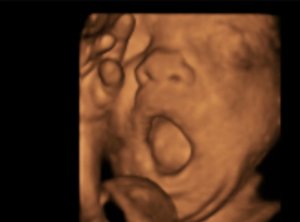

双子妊娠【双子妊娠ブログ】36週の様子!前駆陣痛ってなに? -